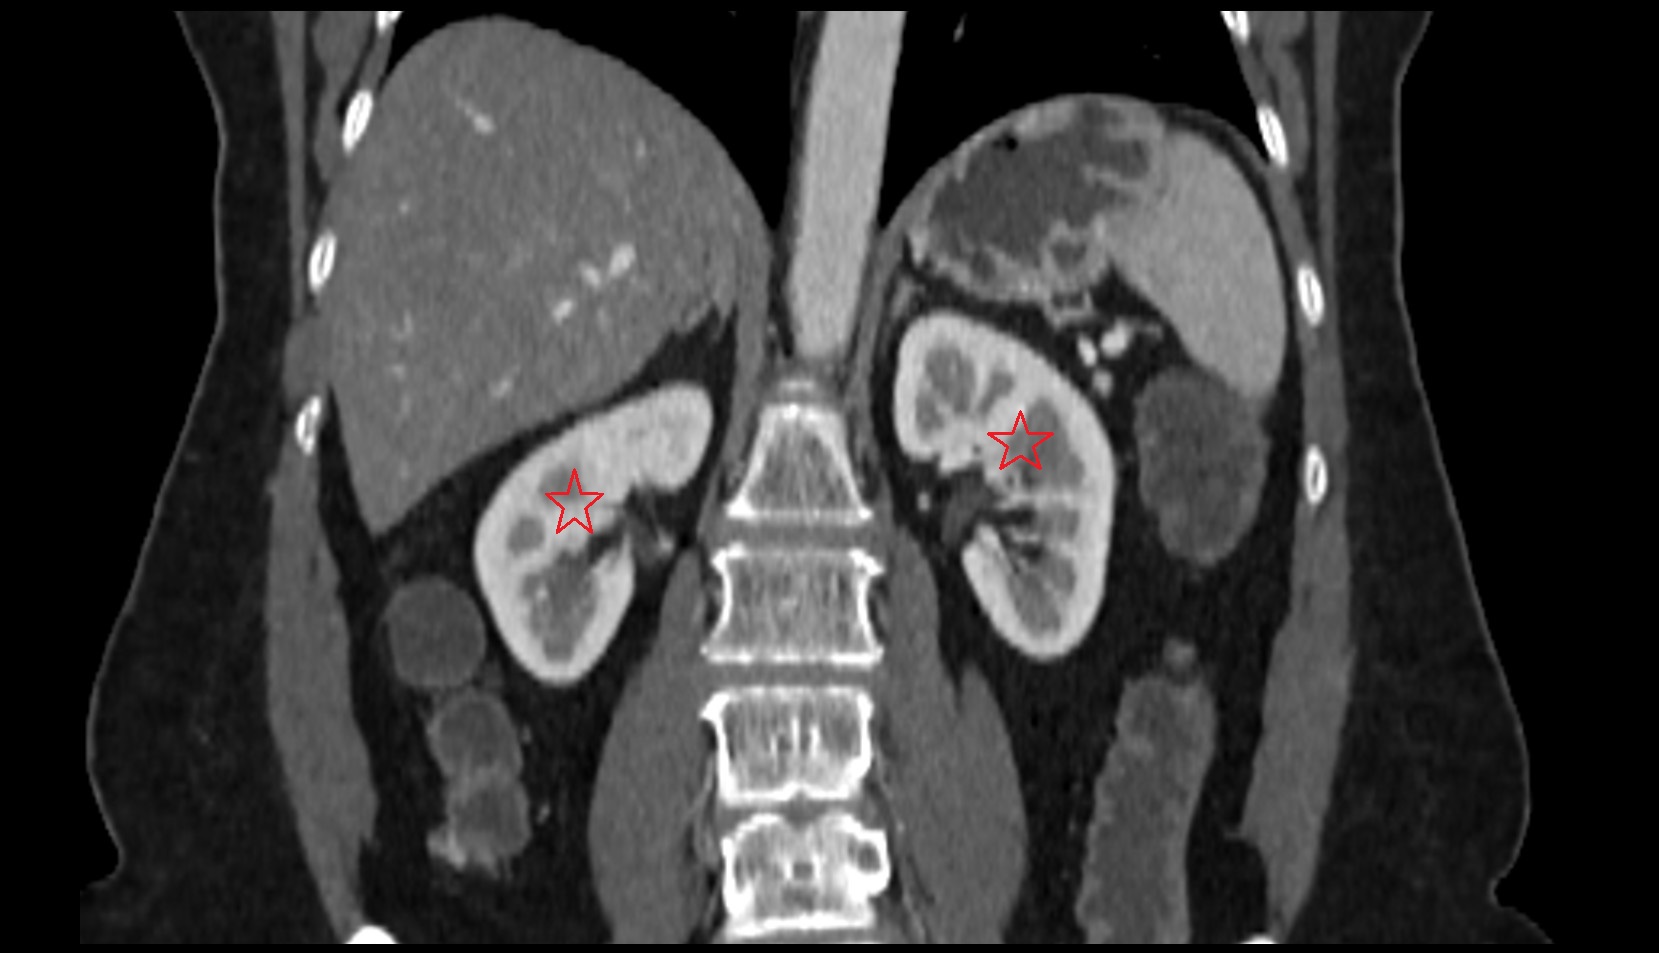

- kidneys

- Right kidney

- Left kidney

- Kidney cortex (Renal cortex)

- Renal medulla

- Renal pyramids

- Adrenal gland

- Ureters

- Left ureter

- Right ureter

- Renal artery

- Renal vein

- Renal pelvis